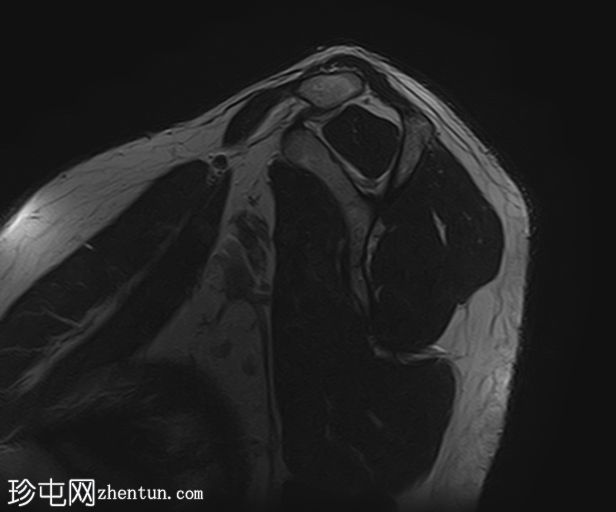

4.jpg

冠状位T2加权像

脂肪抑制像

冈上肌腱上部纤维可见约25 x 1.2 mm的低信号肌腱内病变,符合钙化性肌腱炎的影像学表现

冈上肌腱滑囊侧纤维可见液体信号增高,符合肌腱病

II型肩峰(弯曲型)

肩峰下滑囊内可见轻度液体信号,提示轻度滑囊炎